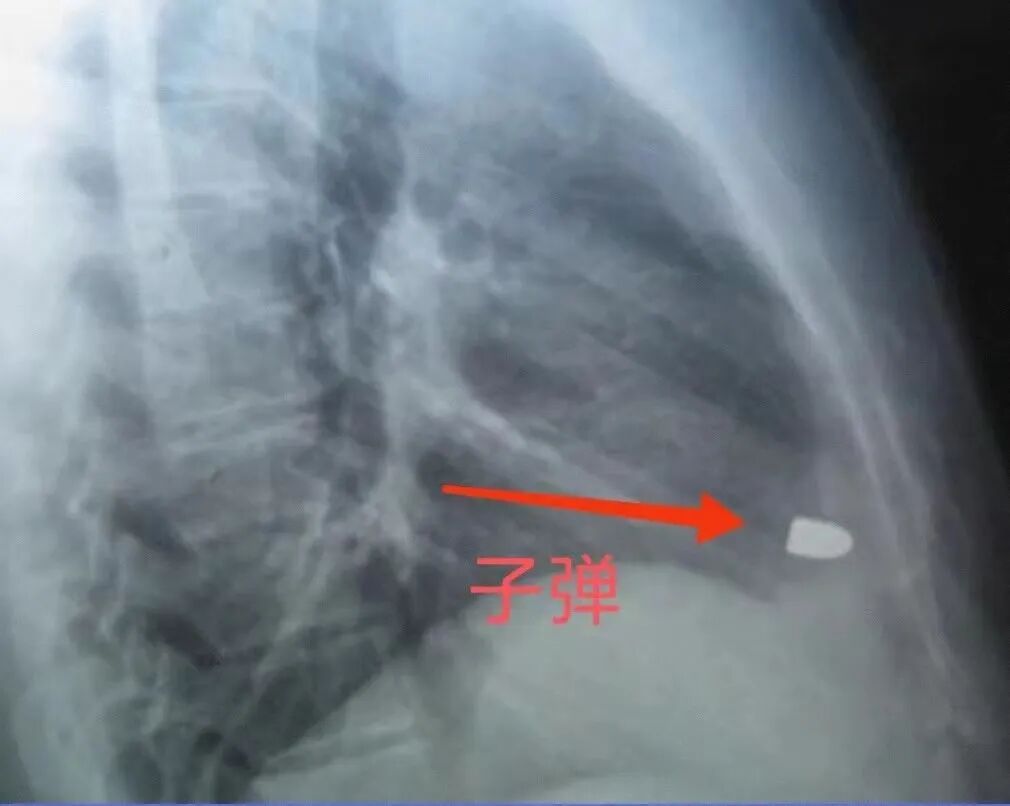

医生给他做了一个X光片,结果出来后发现片子上有一个金属状的白色圆点。

这次他脱掉了衣服,医生还给他做了一个侧方位的X光片,结果却让大家大吃一惊。

脱掉了衣服,片子上依旧出现了一颗白色圆点,而侧方位的片子上可以明显看出这是一颗子弹。

子弹甚至还随着心脏跳动。

在场的医生都不敢相信自己的眼睛,符桂林此时也懵了,但他还是强装淡定地跟医生解释:

“我十四年前被人打过两枪,但当时没找到子弹。”

谁能相信这颗子弹竟然没有让符桂林一枪毙命,甚至还在符桂林的心脏部位待了十四年。